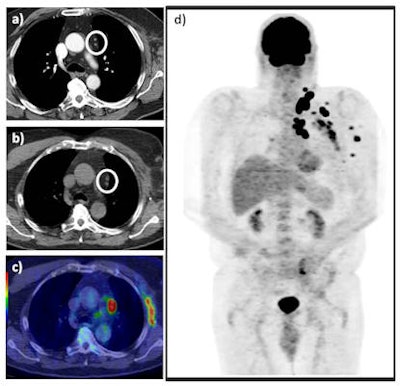

A 73-year-old man with previous recurrent stage IIIC disease was found to have an enlarged fine needle aspiration positive, left supraclavicular lymph node on clinical follow-up. A staging CT revealed presumed postsurgical changes in the left axilla and a couple of sub-5mm mediastinal lymph nodes (white circle) (a). A subsequent FDG PET/CT revealed FDG-avid left axillary soft-tissue recurrence and intensely hypermetabolic sub-cm nodal disease in the mediastinum (white circle) as seen on the axial unenhanced CT (b) and axial fused PET/CT images (c), in addition to multiple further sites of FDG-avid loco-regional disease as seen on the maximum intensity projection (d). This resulted in change from potential radical surgery to chemotherapy, which represented a major clinical impact. All images courtesy of Dr. Manil Subesinghe.The researchers studied 45 patients who were referred for further evaluation with FDG PET/CT. They compared findings on FDG PET/CT with prior contrast-enhanced CT scans, and determined the clinical impact on subsequent management decisions retrospectively. They defined major clinical impact as a change in treatment plan, while minor impact was defined as confirmation of known sites of disease as identified on prior CT.